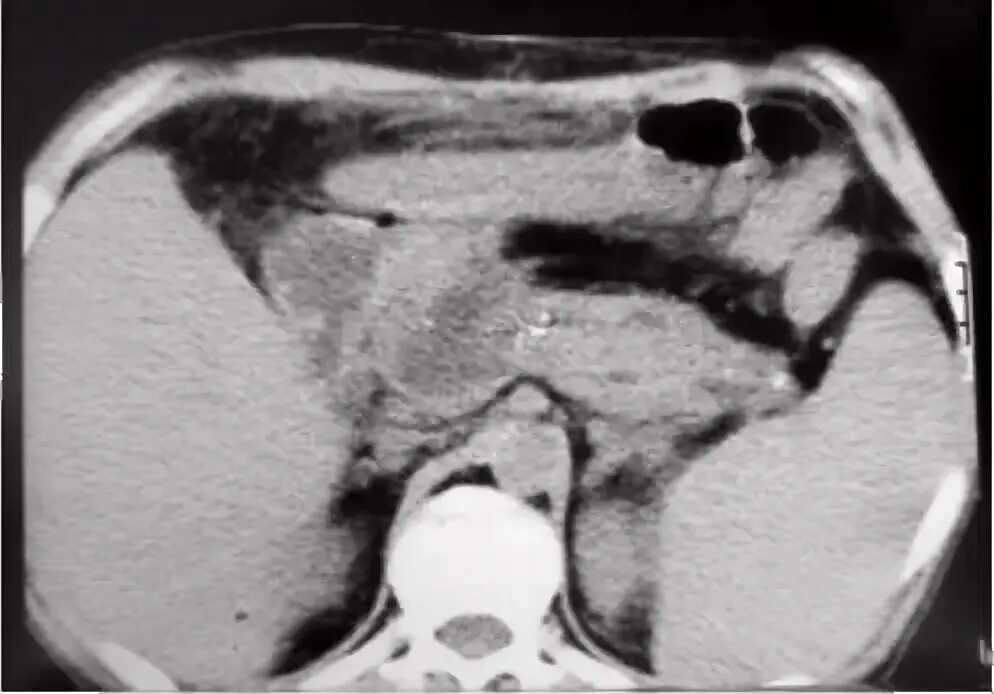

50 лет кт